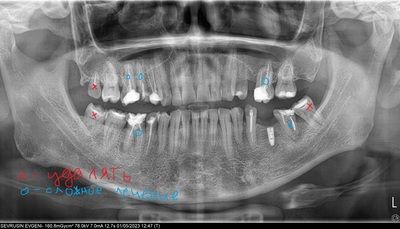

Нахожусь в Аланьи, Турция, и решил вылечить зубы. Обратился в три клиники и все говорят разное. Я ниже напишу их советы и рекомендации, а если среди сообщества есть стоматологи, то пожалуйста, дайте свои советы. Снимок прилагается.

У вас все плохо, нужно срочно удалять два зуба (восьмерка справа сверху и семерка справа снизу). По остальным зубам - везде пломбы начали разрушаться, нужно ставить коронки. Имплант тоже доделать (с этим согласились все три клиники, как и я). В итоге насчитали 11 коронок циркониевых на 2500 евро.

Срочно удалять пятерку, шестерку и восьмерку сверху справа, тройка сверху справа - пломбу делать, семерку снизу справа - пломбу. сверху слева три коронки мостом на промежутке. Но очень странные рекомендации: сначала "срочно удалять", потом "ну, если не беспокоит, то можно и не удалять". Такое ощущение, что подстраиваются под мое мнение, лишь бы только согласился.

У вас неплохие зубы и мы бы не стали ничего удалять, особенно если ничего не беспокоит (меня не беспокоит пока ничего), предлагаем только доделать имплант и поставить коронки мостом над имплантом, там где промежуток. И справа сверху еще три коронки на жевательные. Но типа только для того, чтобы не разрушались. По стоимости 1400 евро за все: 7 коронок и эбатмент.

Если есть профи - оцените, посоветуйте. Мне 41, ничего не беспокоит, но чувствую, что где-то появились сколы, где-то пища попадает между зубов и этот промежуток все больше становится.